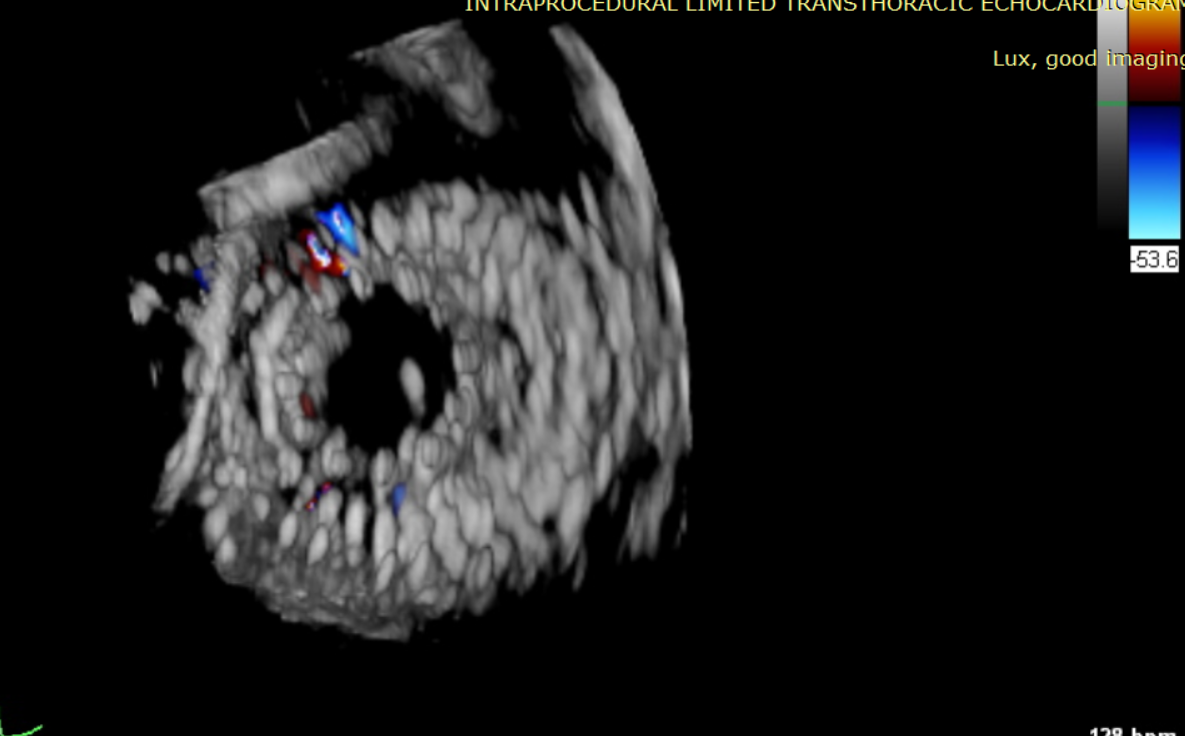

近日,美國紐約Montefiore醫學中心(Montrefiore Medical Center)的Azeem Latib教授團隊成功應用LuX-Valve Plus經血管三尖瓣置換系統為兩位三尖瓣大量反流的患者完成三尖瓣置換手術。術后超聲顯示人工三尖瓣植入穩定,瓣葉啟閉良好,僅殘余微量瓣周漏。患者于手術室即刻拔除氣管插管,血流動力學改善顯著。此次手術是LuX-Valve Plus于紐約的首次臨床應用,治療效果優異。

術后Azeem Latib教授對LuX-Valve Plus經血管三尖瓣置換系統的器械性能和治療效果大為稱贊,并且認為LuX-Valve Plus的手術體驗非常好。從治療效果來看,術后即刻超聲顯示三尖瓣反流幾乎完全消失,血流動力學改善顯著,患者恢復快。在面對復雜解剖結構、超聲影像質量不佳、有起搏導線干擾時,Lux-Valve Plus也體現了極強的適應性。Thomas Modine教授參與了術中指導,他同樣再次肯定了LuX-Valve Plus術中操作的便捷性,認為LuX-Valve Plus容錯率高,對術中影像的依賴小,并表達了后期希望可以更多地應用LuX-Valve Plus三尖瓣置換系統于臨床實踐,讓更多的三尖瓣重度反流患者盡早獲益,改善預后。